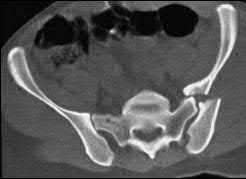

A 35 year-old female presents after prolonged extrication from a motor vehicle collision complaining of severe pelvic pain. Physical examination reveals diminished perianal sensation. She is otherwise neurologically intact. Figures A through D are radiographs and representative CT cuts of her injury. Which of the following nerve roots has likely been injured by the acute trauma?

The clinical scenario is consistent with a high-energy sacral fracture. The radiographs in figures A and B demonstrate a sacral fracture with posterior displacement of the right hemipelvis seen on the inlet view. Figures C and D are axial and sagittal CT images which show a displaced fracture of the right

hemisacrum along with a transvere fracture component through the S3 body . Diminished perianal sensation is concerning for an S2 nerve root injury.

Mehta et al reviewed the current management of sacral fractures. They note that the S1 and S2 nerve roots are more likely to be injured with sacral fractures as they occupy 1/3 to 1/4 of the neural foramina, as opposed to S3 and S4, which only occupy 1/6 of the neural foramina.

Robles reviewed the current literature to ascertain principles of evaluation and treatment for transverse sacral fractures. The author notes that injury to nerve roots S2 to S5 is manifested by impairment of urinary and anal continence and sexual function.

The first illustration demonstrates the sacral nerve root dermatomal distribution. The second shows a pelvic cadaver dissection demonstrating the sacral nerve roots as they exit the foramina.